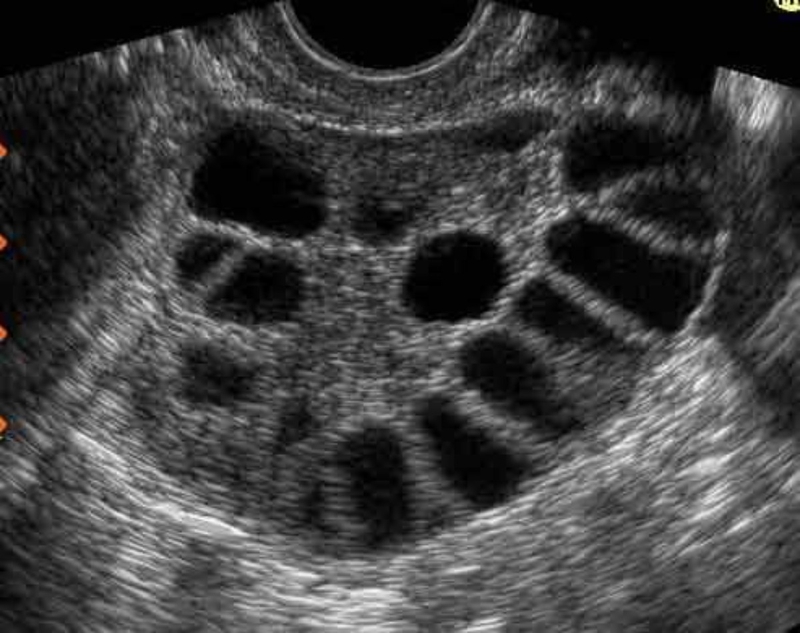

Khối echo trong buồng trứng là một thuật ngữ y học mô tả một dạng nang cơ năng xuất hiện trong buồng trứng của phụ nữ. Đây thường là một loại u lành tính, thường gặp do các biến đổi nội tiết trong cơ thể, đặc biệt là trong quá trình chu kỳ kinh nguyệt.

Một khi khối echo được phát hiện trong buồng trứng, nó thường được đánh giá thông qua các phương pháp hình ảnh y học như siêu âm. Trong các hình ảnh siêu âm, khối echo xuất hiện như một dạng u với mật độ và kích thước khác nhau. Điều này thường xảy ra ở các giai đoạn khác nhau của chu kỳ kinh nguyệt, từ giai đoạn phóng noãn đến cuối chu kỳ, khi các nang cơ năng trong buồng trứng phát triển hoặc tự tiêu đi.

Mặc dù hầu hết các khối echo trong buồng trứng là u lành, nhưng có trường hợp nếu chúng phát triển quá lớn hoặc gây ra các triệu chứng không mong muốn, có thể cần đến sự can thiệp y tế. Do đó, việc đánh giá và theo dõi các khối echo trong buồng trứng là một phần quan trọng trong quá trình chăm sóc sức khỏe của phụ nữ.

Khối echo trong buồng trứng